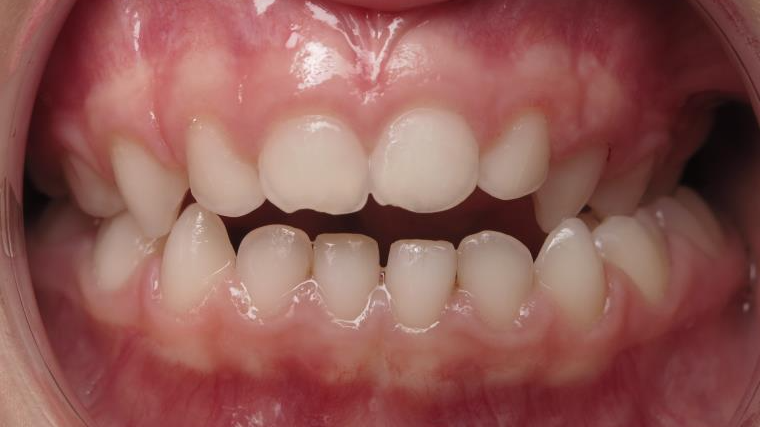

14 béance inversé gauche 5 ans

inversion postérieur coté droit et espace entre l'arcade du haut et du bas (béance)